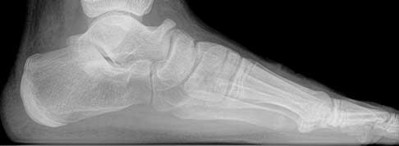

Figures 1a through 1c

Tarsal coalitions occur when primitive mesenchymal cells fail to differentiate and form the

normal articular separations between the tarsal bones of the hindfoot. Overall incidence is difficult to determine because many affected people are minimally symptomatic or asymptomatic. Symptomatic tarsal coalitions typically present in adolescents as a painful flatfoot; however, there are a number of possible presentations, and occasionally symptoms do not appear until adulthood. Most tarsal coalitions are between the calcaneus and the navicular (CN) and the talus and the calcaneus (TC). Although most TC coalitions are across the middle facet, posterior facet coalitions do occur. Plain radiographic evaluation of suspected tarsal coalition is the mainstay for diagnosis. However, coalitions can be bony or fibrous, and making the diagnosis can be difficult. The addition of CT images to distinguish bony definition and MR images to decipher soft tissue can aid in diagnostics. Bony coalitions appear as definite bony bridging between the bones, while fibrous coalitions are suspected when distortion of the bony anatomy is seen. Bony coalitions are best seen on the oblique view (CN) and Harris axial view (TC). There are a number of secondary signs such as the anteater (AE) sign (elongation of the anterior process of the calcaneus as it extends to the navicular as seen on the lateral view [CN]). talar beaking (traction spur of the talar neck thought to result from abnormal stresses as seen on the lateral view [both CN and TN]), and the “C” sign (a continuous cortical contour from the medial talus to the sustentaculum tali [ST]) as seen on the lateral view (TC). A number of newer signs are not as well known, such as a broad mediolateral dimension of the navicular on the anteroposterior (AP) view (the

navicular is wider than the talar head [CN]), nonvisualization of the middle facet on the lateral view (TC), the brick sign (a normal ST is flat, but a distorted ST is enlarged and curved [CN]), and a tapered lateral navicular bone as seen on the AP view (the medial navicular [CN] is much thicker than the lateral navicular).

Figure 1a shows talar beaking (TB), an AE, and an open middle facet (MF). Figure 1b shows a wide navicular (WN), and Figure 1c shows an abnormal articulation between the calcaneus and the navicular, all consistent with a CN coalition.